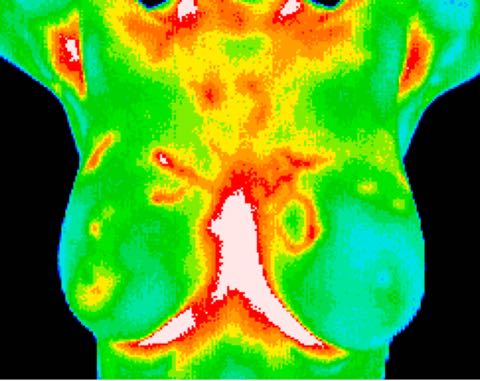

DCIS (1 of 3 of this study) medial left breast